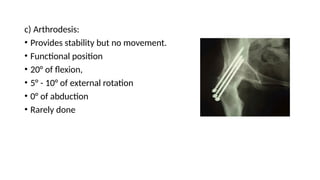

c) Arthrodesis:

• Provides stability but no movement.

• Functional position

• 20° of flexion,

• 5° - 10° of external rotation

• 0° of abduction

• Rarely done